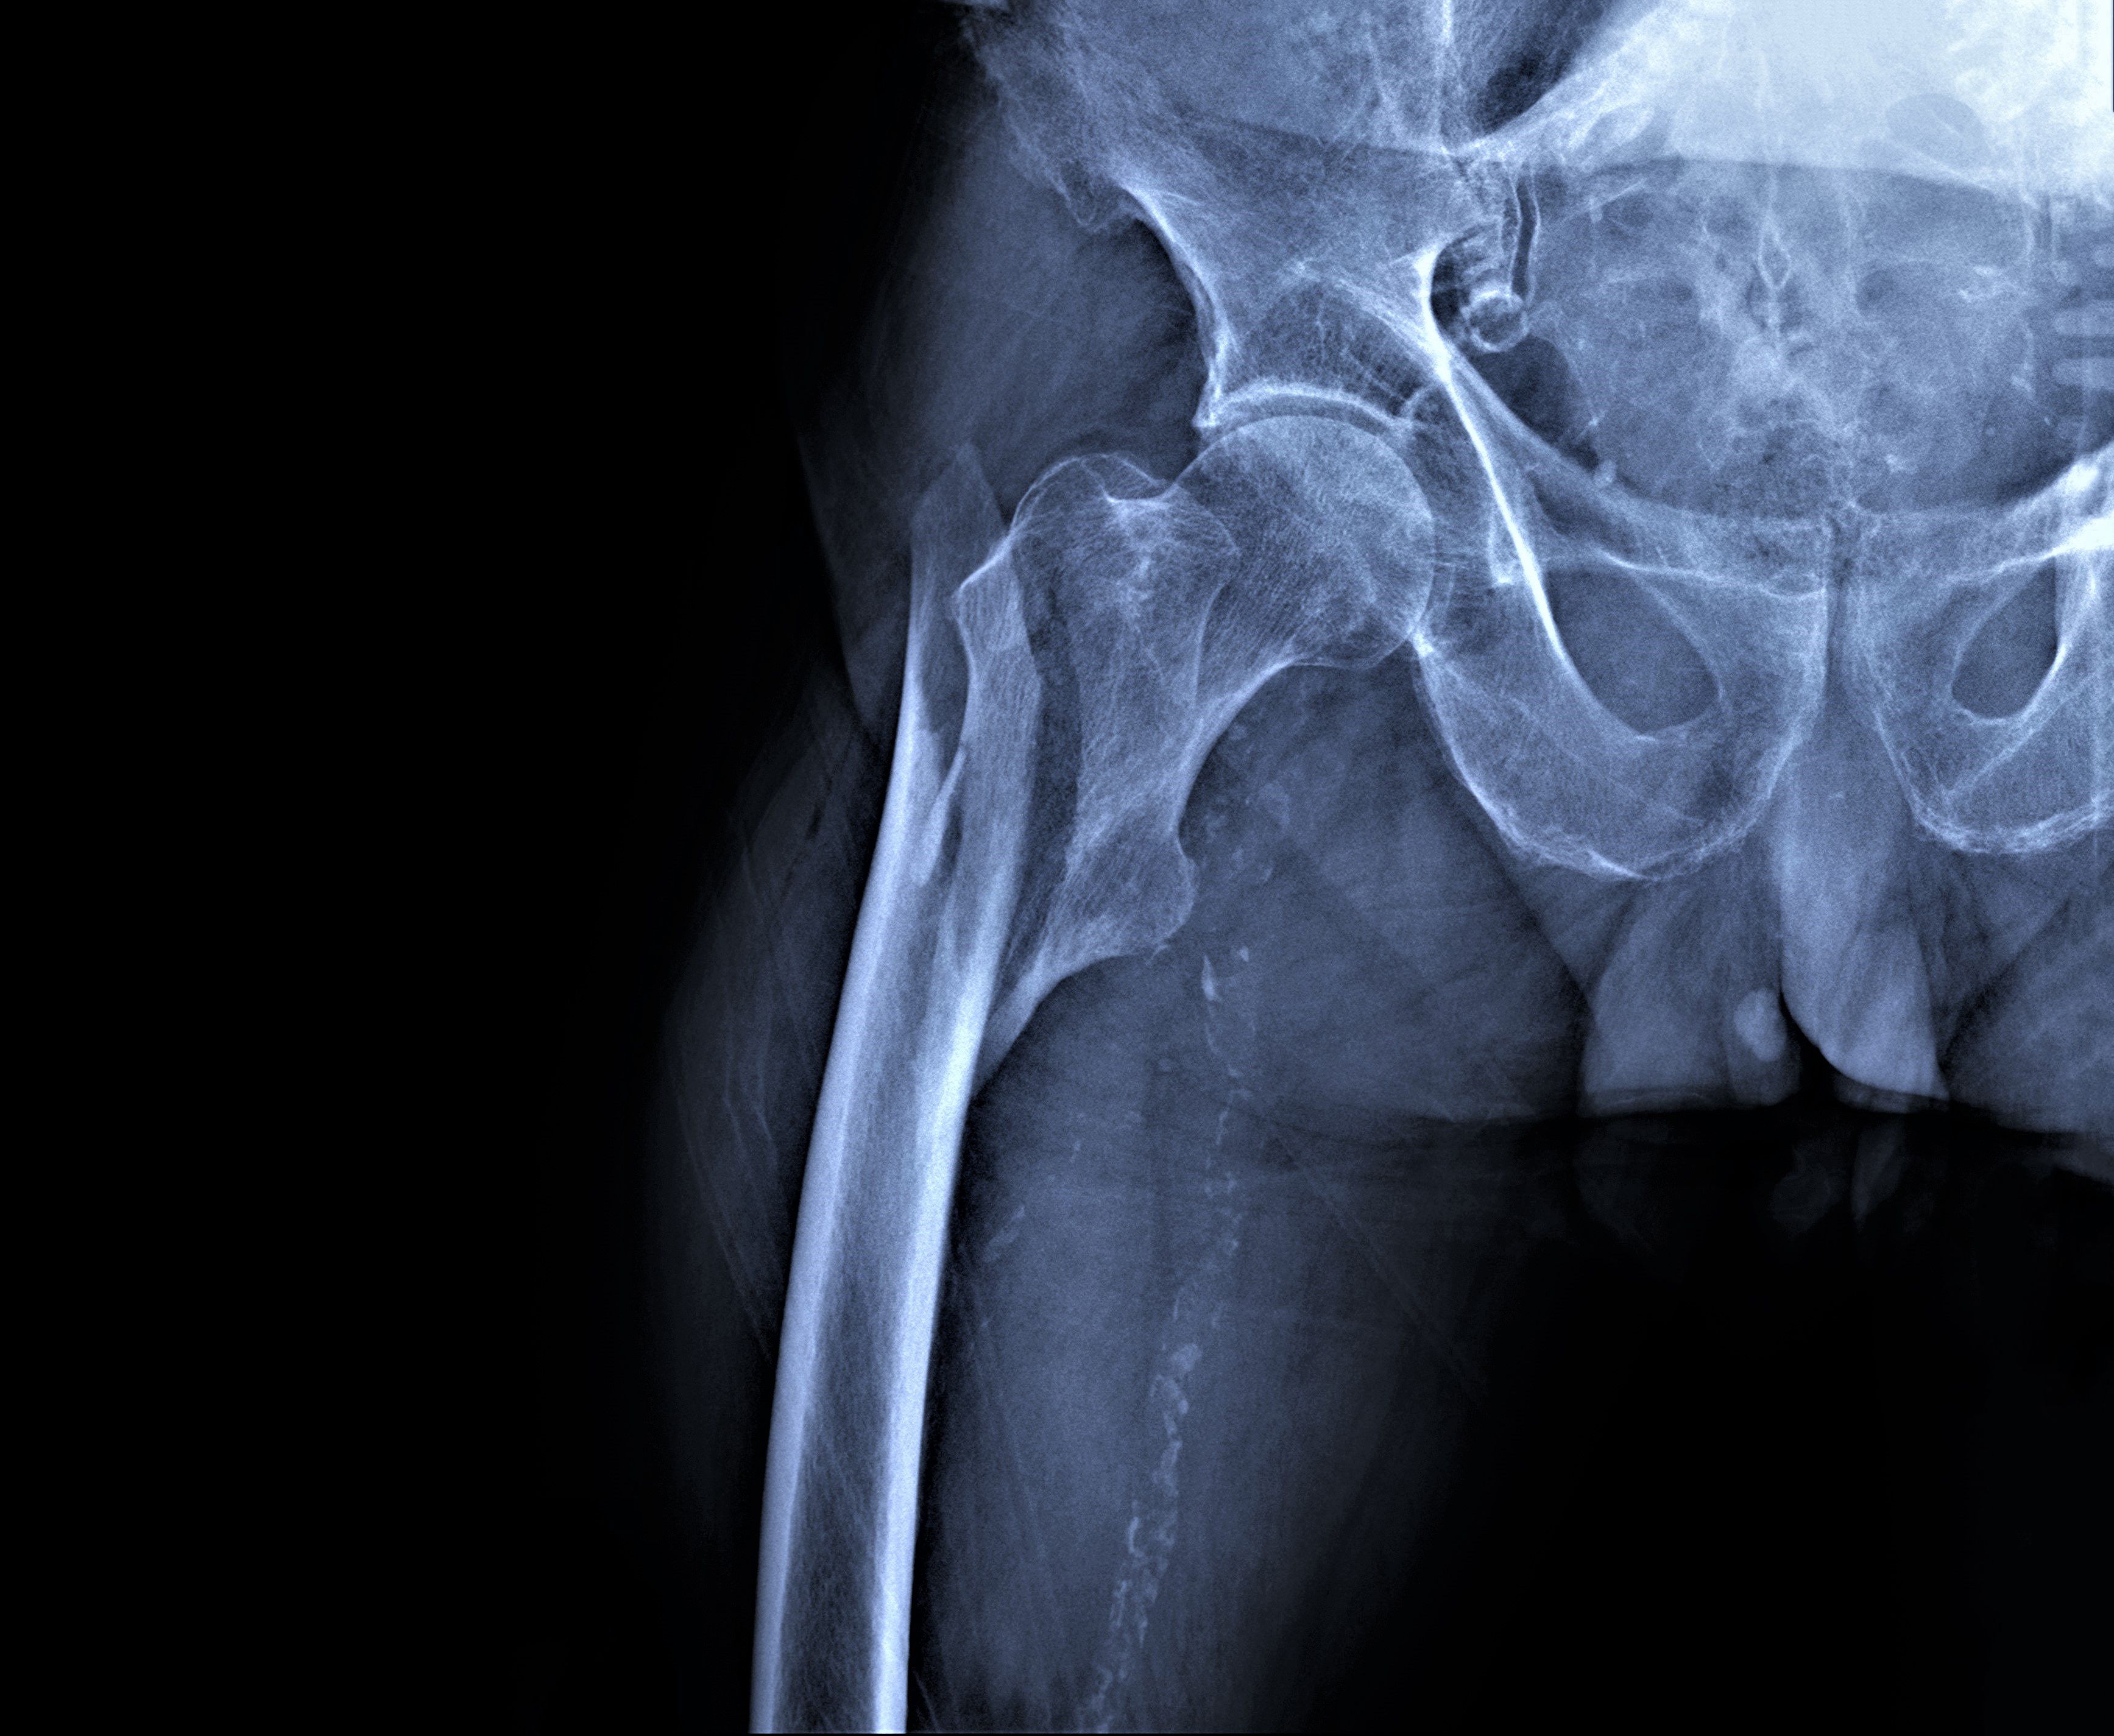

Impact of blood flow restriction on bone markers during resistance training

A 12-week course of low-intensity resistance training in postmenopausal women with osteoporosis or osteopenia was found safe and an effective method to improve muscle strength, bone formation markers and balance, according to a study in the Journal of Exercise Science and Fitness.

No changes were observed in bone mineral density (BMD) in the three exercise groups, but the control group showed a significant decrease in BMD (P < 0.05).